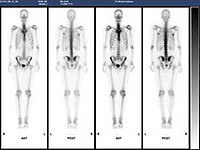

骨シンチ